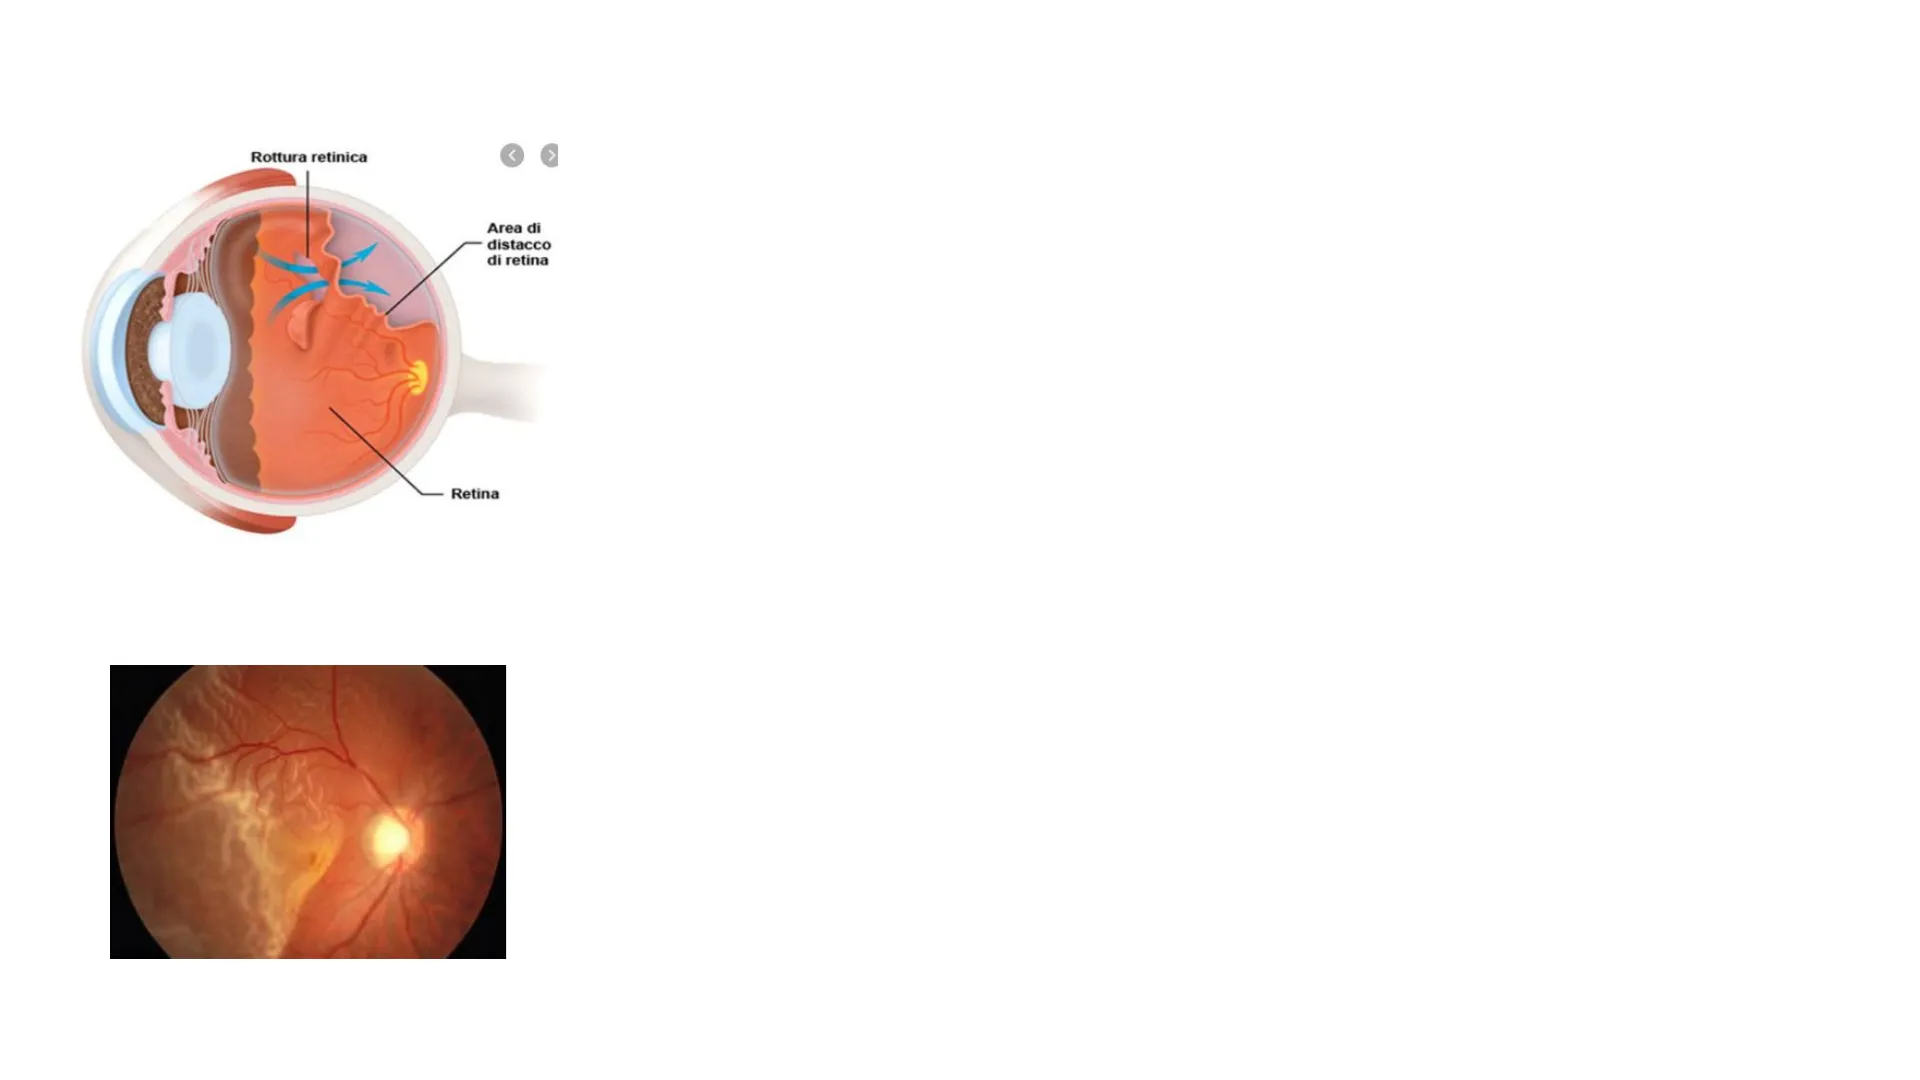

La retina è formata da 2 foglietti: Rottura retinica Area di distacco di retina Retina L'epitelio pigmentato e il foglietto neurale (costituito da cellule nervose) I 2 foglietti non sono saldati ma ben accostati, grazie a un'azione di pompa dell'epitelio pigmentato, sui liquidi presenti tra i 2 foglietti, si crea effetto a ventosa che li tiene accostati. Il distacco di retina si verifica quando il foglietto neurale (neuroretina) si separa dal sottostante tessuto di sostegno (epitelio pigmentato retinico). È uno sdoppiamento della retina Questa è una condizione molto grave R. Siciliano

Rottura retinica Area di distacco di retina Retina Distacco di retina La causa più frequente del distacco di retina è la rottura retinica (distacco regmatogeno; règma = rottura), cioè si vengono a formare piccoli fori o lacerazioni, o per la presenza di aree di degenerazione che rendono fragile o sottile la retina o a causa di aderenze anomale e forze di trazione. Il corpo vitreo liquefatto (miopia, senilità) penetra nello spazio tra i 2 foglietti e ne provoca la separazione La neuroretina gradualmente perde l'aderenza con l'epitelio pigmentato, sollevandosi. R. Siciliano

Rottura retinica > Area di distacco di retina Retina Distacco di retina In un raro numero di casi, il distacco, può essere impedito da cicatrici spontanee della rottura. Ciò è più probabile quando la lesione è nella parte inferiore della retina. X < Quando la lesione è nella parte superiore della retina, il liquido infiltrato tende a scendere per effetto della gravità e il distacco si estende. R. Siciliano